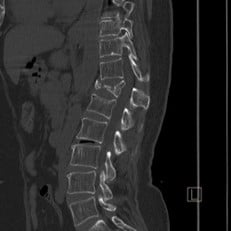

Case courtesy of Dr Hani Makky Al Salam, Radiopaedia.org, rID: 18568

Given the patient’s history of a fall along with spinal tenderness, you order an x-ray that shows an acute T12 compression fracture. Subsequent CT imaging shows an absence of ligamentous injury or cord involvement. Pain control is achieved using IM ketorolac, a lidocaine patch, and calcitonin nasal spray. Spine surgery is consulted and recommends non-operative management. The patient is instructed to follow up with her primary care physician and spine surgeon and endorses understanding.